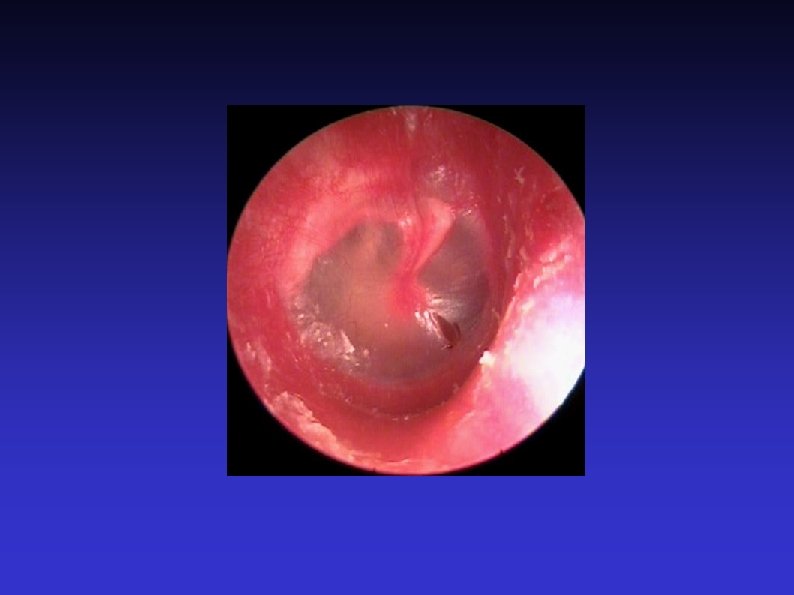

Examination of the Ear 7) Otoscopic examination The lateral process and handle of the malleus lie towards the centre of the tympanic membrane Four quadrants Perforation Central or marginal What can be seen through it Mastoid cavity Dry Wet, inflamed